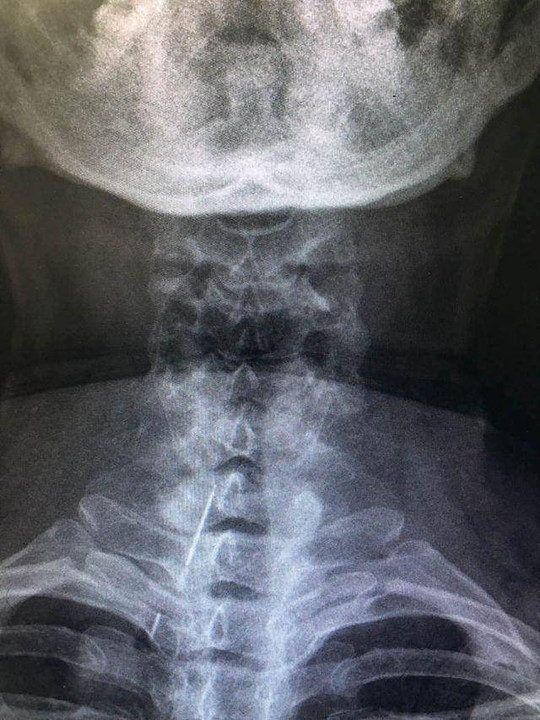

����� �������Ƴ������������ �������Ƴ������������ �������Ƴ������������ �������Ƴ������� 如果不是声音����� �������Ƴ������������ �������Ƴ������������ �������Ƴ������������ �������Ƴ�������哑了卢阿姨还不会去医院看!在胸片检查的时候����� �������Ƴ������������ �������Ƴ������������ �������Ƴ������������ �������Ƴ������,放射科医生竟意外发现,卢阿姨的颈部有一枚����� �������Ƴ����������� �������Ƴ������������ �������Ƴ������������ �������Ƴ�������细长的异物,看形状像是绣花针,而且已经断成����� �������Ƴ������������ �������Ƴ������������ �������Ƴ������������ �������Ƴ�������了三截!

����� �������Ƴ������������ �������Ƴ������������ �������Ƴ������������ �������Ƴ�������;5月5日上午,经半个多小时手术,医生从卢阿����� �������Ƴ������������ �������Ƴ������������ �������Ƴ������������ �������Ƴ�������姨脖子内取出了这3截满是锈迹的针。